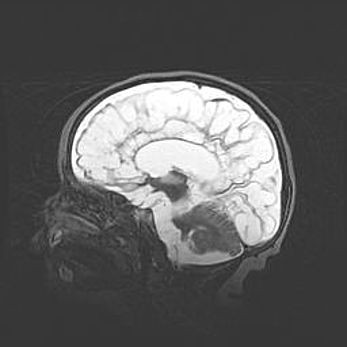

Церебральная ишемия II.

Возраст: 5 дней

Вес: 3400 г

Пол: женский

Окружность головы: 35 см

Срок гестации: 39 недель

Церебральная ишемия – это заболевание, характеризующееся недостаточностью (гипоксией) либо полным прекращением (аноксией) снабжения мозга кислородом по причине закупорки одного или нескольких сосудов. Это приводит к  что метаболическим расстройствам различной степени тяжести в тканях головного мозга, развитию коагуляционных некрозов и гибели нейронов.